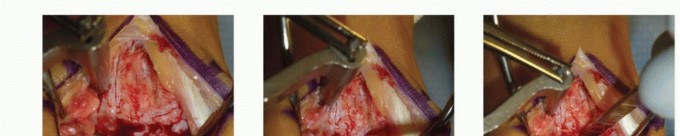

1. Medial Malleolar Osteotomy (For Medial Lesions)

Medial lesions are typically located centrally or posteriorly on the medial talar dome. A medial malleolar osteotomy provides unparalleled perpendicular access.

- Make a longitudinal incision over the medial malleolus.

- Expose the medial malleolus, protecting the posterior tibial tendon and neurovascular bundle posteriorly.

- Pre-drill two holes for 4.0-mm partially threaded cancellous screws to ensure perfect anatomic reduction during closure.

- Perform a chevron-type or step-cut osteotomy using an oscillating saw, completing the final articular cut with an osteotome to preserve the cartilage.

- Reflect the medial malleolus inferiorly on its deltoid ligament hinge.

2. Anterolateral Approach (For Lateral Lesions)

Lateral lesions are generally located more anteriorly and can often be accessed without an osteotomy.

* Approach lateral lesions through an anterior sagittal incision.

* Perform an anterolateral arthrotomy. Extreme plantarflexion of the ankle usually brings the lateral lesion into view.

* Note: Rarely, a lateral malleolar osteotomy or fibular window is required to access far posterolateral lesions.